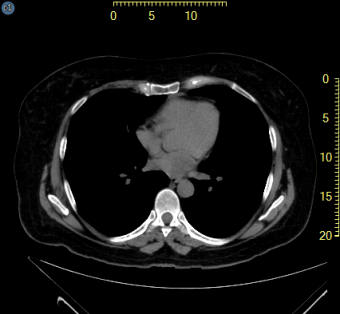

A képkocka külső részén megjelenő vonalzó overlayek az összes kalibrált képre vonatkozóan léteznek, amint az alább sárga színnel kiemelve látható. A felhasználó beállíthatja a vonalzók helyét és azt, hogy függőlegesen, vízszintesen vagy mindkét síkban helyezkedjenek el.